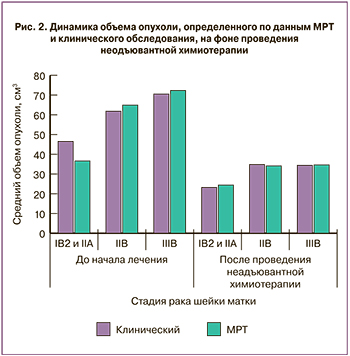

Объем опухоли шейки матки, определенный при физикальном обследовании пациенток до начала терапии, при IB2 и IIA2 стадиях заболевания составлял от 28,1 до 131,0 см3 (46,5 (19,4) см3), при IIB стадии – от 24,2 до 152,9 см3 (61,8 (27,8) см3), IIIB – от 35,1 до 152,9 см3 (70,5 (23,6) см3).

При МРТ-исследовании до начала специального лечения объемы новообразований при IB2 и IIA2 стадиях РШМ составили от 3,0 до 73,3 см3 (36,6 (17,0) см3), при стадии IIB – от 32,2 до 103,1 см3 (64,9 (19,9) см3), при IIIB стадии – от 32,2 до 145,1 см3 (72,3 (23,6) см3) (рис. 1).

Через 14 дней после проведения химиотерапии физикальное обследование у больных РШМ стадий IB2 и IIA2 показало уменьшение размеров опухоли до 23,2 (16,6) см3 (на 50,1%). При IIB стадии удалось достигнуть объема новообразования 34,8 (18,0) см3 (разница с показателем до начала лечения 43,7%), при IIIВ – 34,4 (12,4) см3 (уменьшение на 51,2%).

Через 14 дней после проведения химиотерапии физикальное обследование у больных РШМ стадий IB2 и IIA2 показало уменьшение размеров опухоли до 23,2 (16,6) см3 (на 50,1%). При IIB стадии удалось достигнуть объема новообразования 34,8 (18,0) см3 (разница с показателем до начала лечения 43,7%), при IIIВ – 34,4 (12,4) см3 (уменьшение на 51,2%).

По данным МРТ, после проведения химиотерапии при IB2 и IIA2 стадиях РШМ объем опухоли уменьшался до 24,4 (19,7) см3 (на 33,3%). При IIB стадии заболевания объем новообразования достигал 34,1 (16,5) см3, уменьшаясь на 47,5%. При IIIB стадии данный показатель оказался 34,6 (11,5) см3 (разница с показателем до начала лечения 52,1%; рис. 2–3).

Выявлена высокая прямая корреляционная зависимость размеров новообразования, определенных при клиническом исследовании и МРТ у больных местнораспространенным РШМ до начала лечения и после проведения неоадъювантной химиотерапии (r=0,735382).